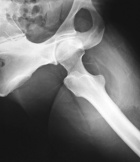

J.R. - 45 year old female with large buttock mass

Zoom image: Radiological image Radiological image.